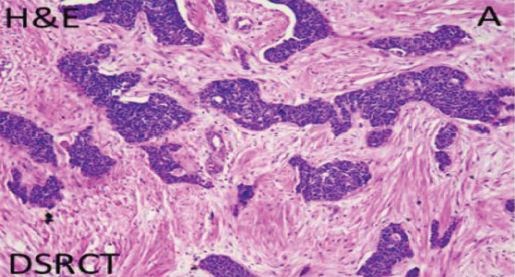

Continuing with the theme of being first, one task that I really wanted to complete and that I was determined to accomplish was to treat a very rare cancer, desmoplastic small round cell tumor (DSRCT) (see Figure 1). It turns out I would become the first person to do so. This operation lasts 14–20 hours, and hundreds of tumors are removed; in fact, the most that have been removed was nearly 2,000 tumors. Why did I want to do this? Why did I want to tackle something like this rare tumor? And why hadn’t it been solved before?

FIGURE 1. DSRCT

UT MD Anderson Cancer Center

This complex tumor is composed of fibrous strands, which makes it quite difficult to treat. It has a 10% survival rate. I wanted to change the outcome of this disease. I wanted to do something different. Many people said I couldn’t do it. They said, “You know this type of disease is very rare, incurable, and there’s nothing we can do about it.” I said, “Well, maybe we can try doing something like this hyperthermic intraperitoneal chemotherapy (HIPEC) after removing all of the tumors.” My adult colleague said it would be impossible, and my pediatric colleague agreed, so I had to persevere.